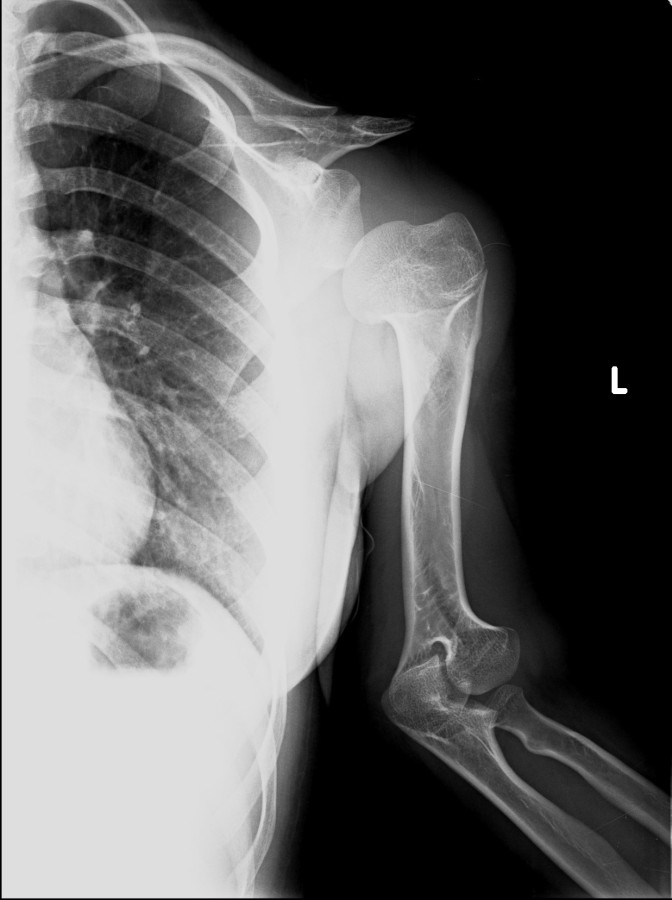

13-15 yaşlar arasında Her iki humerusu (kol) 8-12 cm boy uzatma Dirseklerin fleksiyon deformitesini düzeltme Ortalama eksternal fiksasyon tedavi süresi = 6-8 ay Alt uzuvların iki uzatması arasında üst uzuvlar uzatılarak alt uzuvların dinlenmesi sağlanmış olur. Cihaz çıkartıldıktan sonra en erken ikinci uzatmaya başlama süresi 6 aydır. Bilateral femoral uzatmalarda uzatma fazı sırasında hastanın yürümesi mümkün değildir. Ayakta durmaya sadece hasta transferi sırasında izin verilir. Uzatma fazında ambulasyona sadece tekerlekli sandalye ile izin verilir. Konsolidasyon fazında ise tedrici olarak daha fazla yük verilmesine ve cihazın çıkmasına yakın serbest yürümeye izin verilir. Bilateral tibial uzatmalarda ilk günden itibaren yürüteç veya koltuk değneği ile hastanın yük vermesine izin verilir. Uzun gezintiler tekerlekli sandalye ile yapılmalıdır. Bilateral humeral uzatmalarda hemen hemen hiçbir aktivite kısıtlaması yoktur. Uzatma süresince her iki haftada bir yapılan takiplerde kantitatif duyusal sinir testleri doktor tarafından yapılmalıdır. Bu gelişmekte olan sinir sorunlarını klinik olarak ortaya çıkmadan yakalamaya izin verir. Femoral ve humeral uzatmalarda çok nadir görülmesine rağmen tedavi edilmedikleri durumda düşük ayağa (ayağı yukarı çeken kasları innerve eden sinirin felci) neden olabilirler. Eğer erken tespit edilir ve uzatmanın hızı azaltılırsa, sinir problemi genellikle kendiliğinden düzelir ve uzatmaya düşük hızda devam edilir. Uzatmada yavaşlamaya rağmen sinir problemi devam ederse sinirin cerrahi olarak gevşetilmesi gerekir. Bu işlem 1cm’ lik bir kesi ile yapılabilen ve hastanede bir gece kalmayı gerektiren küçük bir işlemdir. Bu ameliyat el bileğinde sinir sıkışması (karpal tünel sendromu) için yapılana benzerdir.